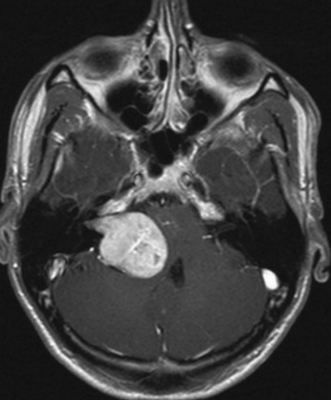

Вестибулокохлеарный нерв (VIII) состоит из 4 пучков. Опухоли происходят обычно из вестибулярной его части. Шваннома - инкапсулированная доброкачественная (градация 1) опухоль, происходящая из дифференцированных неопластических шванновских клеток оболочек периферических нервов. Невриномы ММУ составляют около 3% опухолей головного мозга. Часть шванном (двухсторонние слуховых нервов) связана с НФ 2 типа. Пик частоты между 40 и 60 годами. Растут медленно и крайне редко малигнизируются. Клинические проявления связаны с нарушением функции нерва и компрессией ствола. Шваннома может происходить из любого отрезка по ходу нерва и хорошо прослеживается при МРТ области ММУ. Невринома видна как на Т2-взвешенных, так и на Т1-взвешенных МРТ в виде округлого образования. Невриномы хорошо и равномерно усиливаются после МРТ с введением контрастного вещества. Невриномы области цистерны могут иметь компонент во внутреннем слуховом проходе, особенно, хорошо видимый при МРТ головного мозга с контрастированием. Изредка встречаются невриномы полностью расположенные внутри канальца. Они составляют наибольшую диагностическую сложность при МРТ, требуют тонких срезов и контрастирования. Менингиомы ММУ обычно типично расположены и при МРТ имеют характерную форму и типичные черты при МРТ с контрастированием. Однако редко встречаются внутриканальцевые менингиомы. При МРТ они неотличимы от неврином. Холестеатомы при МРТ имеют смешанную интенсивность сигнала, в зависимости от их содержимого. На диффузионно-взвешенных МРТ холестеатомы обычно яркие.

Шваннома (невринома) представляет собой инкапсулированную доброкачественную (градация I) опухоль, происходящую из дифференцированных неопластических шванновских клеток оболочек периферических нервов. Растут шванномы медленно и крайне редко малигнизируются. В целом шванномы составляют примерно 8% от внутричерепных опухолей. Пик частоты приходится на возраст 40-60 лет. Чаще всего встречаются шванномы слухового нерва (VIII пара), они составляет около 80 - 90% всех опухолей мосто - мозжечкового угла и около 3% от внутричерепных опухолей. Невриномы происходят из дистального по отношению к входу во внутренний слуховой проход части слухового нерва, обычно из вестибулярной (верхней) его ветви. Двухсторонние невриномы наблюдаются в 5% случаев и связаны с нейрофиброматозом типа II. Поскольку слуховой нерв (VIII пара) и лицевой нерв (VII пара) тесно связаны в начальной части, то на МРТ эти опухоли не дифференцируются. В 7-10% случаев шванноме сопутствует арахноидальная киста. Нейрофибромы отличаются от неврином большим числом соединительнотканных и нервных волокон, а также отсутствием капсулы. Пик частоты приходится на возраст 40-50 лет. Опухоль несколько чаще встречается у женщин. Для неврином слухового нерва характерна сенсоневральная тугоухость, шум в ушах и нарушение равновесия.

На Т2-взвешенных МРТ головного мозга невриномы имеют округлую или овальную форму, изоинтенсивны или слегка гиперинтенсивнее белого вещества, хорошо видны на фоне яркого ликвора цистерны. Крупные опухоли могут подвергаться кистозной дегенерации и включать сосуды. Мелкие невриномы имеют компонент во внутреннем слуховом проходе и как бы “утолщают“ нерв на МРТ изображениях. Как показывает опыт МРТ СПб полностью внутриканальцевые невриномы встречаются редко. МРТ в СПб при шванномах мы проводим обычно с контрастированием. Контрастирование неврином при МРТ с контрастированием хорошее, обычно однородное. Нельзя забывать, что во внутреннем слуховом проходе также может быть воспалительный процесс (неврит), приводящий к сходной клинической симптоматике. При МРТ неврит виден как отёк нерва, имеется контрастное усиление на МР томограммах.

МРТ головного мозга. Невринома слухового нерва слева с внутриканальцевым компонентом. Аксиальные Т1-зависимая МРТ, Т1-зависимая МРТ с контрастированием, и корональная Т1-зависимая МРТ с контрастированием.

Невринома слухового нерва в цистерне и внутреннем слуховом проходе. Киста (чёрная стрелка). Аксиальная Т1-взвешенная МРТ, неоднородное контрастирование.

МРТ головного мозга. Полностью внутриканальцевая невринома слухового нерва. Аксиальная Т2-зависимая МРТ, дефект на фоне СМЖ.